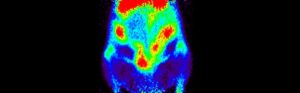

Just as it is possible to label a drug to find out whether it crosses the blood-brain barrier and then to measure the uptake and washout kinetics into the brain, it is also possible to use the labeled drug to measure uptake elsewhere. In this case the question is whether a drug reaches a fetus across the placental barrier. Reasons can include a desire to treat the fetus, or a desire to choose a drug partly on the basis of its exclusion from the fetus to minimize fetal toxicity and teratogenicity. These examples show selected images obtained from a study of live pregnant rats injected with I-124 labeled drug at 8, 11, 12 and 20 days of gestation. Injections were done at varying times, images shown are primarily of the abdomen only.

The “string of pearls” image of the fetuses is visible in the images. The rats had at least nine fetuses. From the whole-animal image at 8 days it is clear that this molecule did NOT accumulate well in the uterus or fetuses. The vast majority of administered dose was excreted. This can be a good result, of course. Further, uptake in this case appears to be in the placental areas and not in the uterine wall or contained within the fetuses.